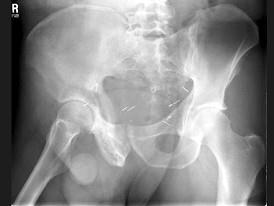

问题 男,56岁,右髋部疼痛,5年前被确诊为前列腺癌,结合图像,最可能的诊断是?(?)

选项 A.骨纤维异常增殖症 B.转移性骨肿瘤 C.畸形性骨炎 D.内生软骨瘤 E.非骨化性纤维瘤

答案 C